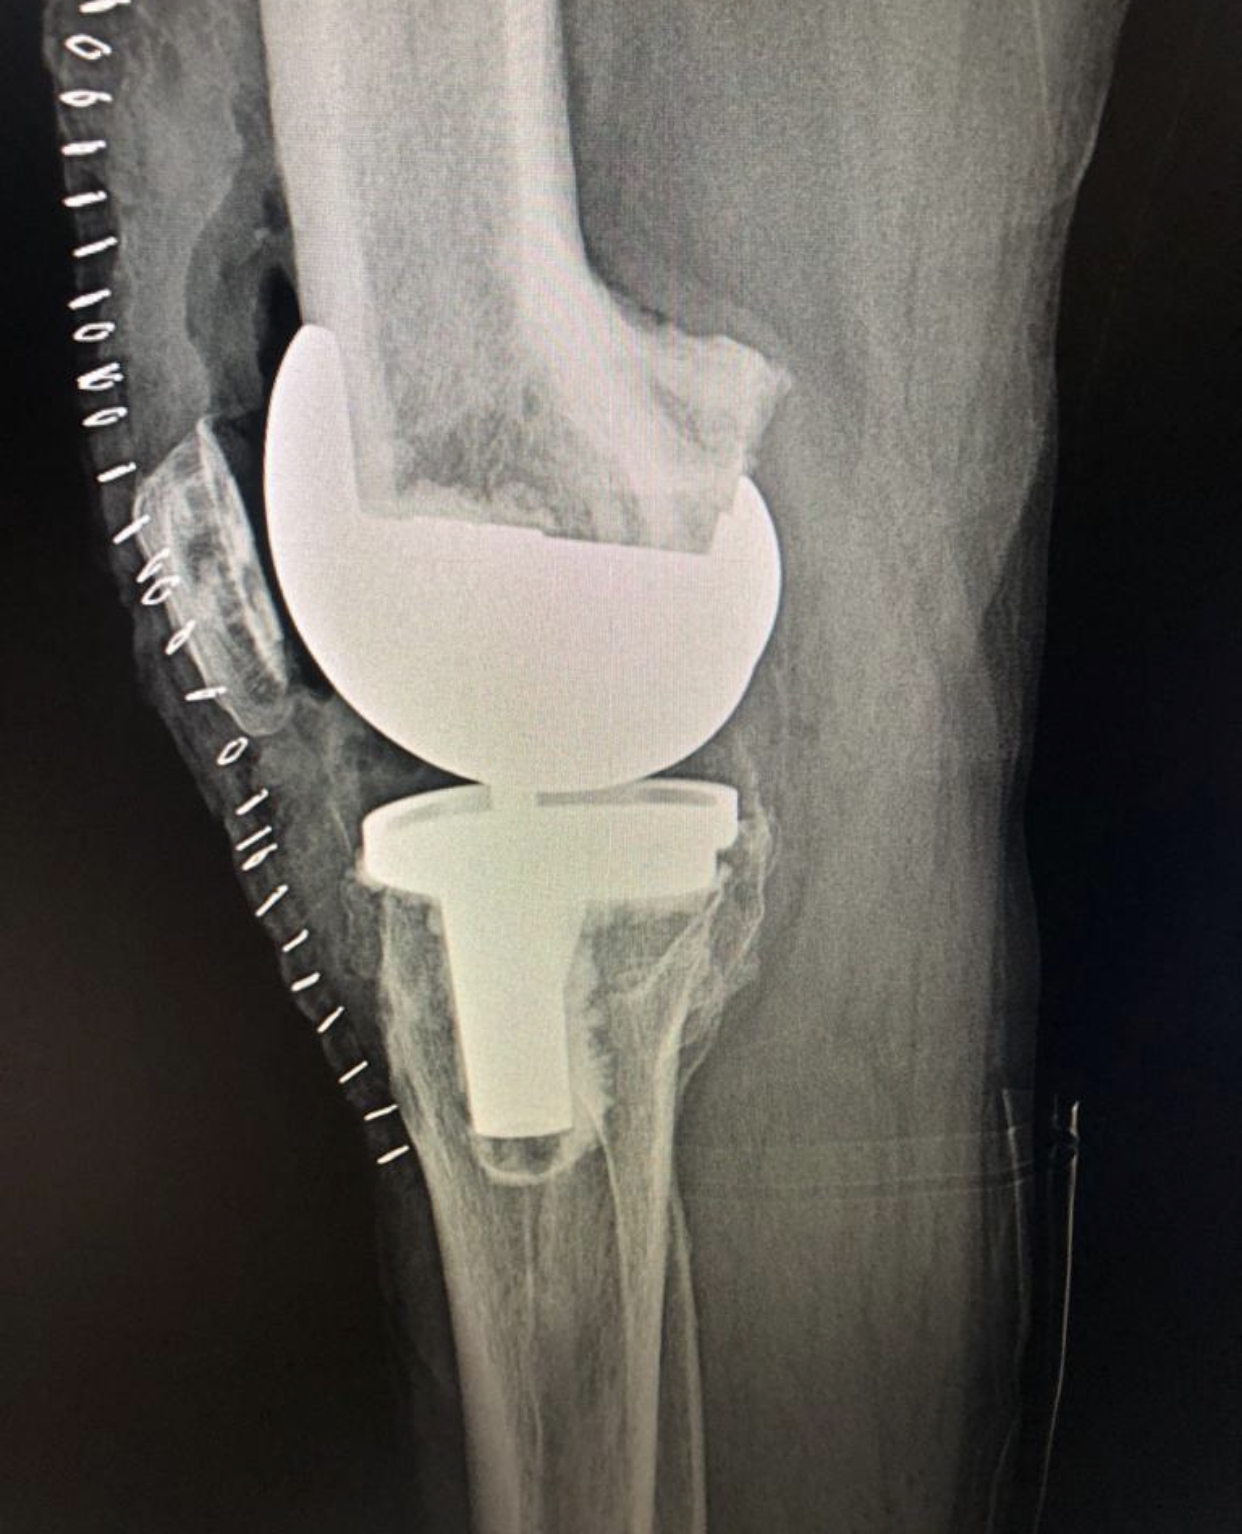

Paget’s disease with bowed femur 12 degrees Varus and 12 degrees flexed

The options of navigated and robotic replacement were offered. Settled for a simpler local custom made distal cutting jig , followed by gap method for a Varus valgus stabilised knee